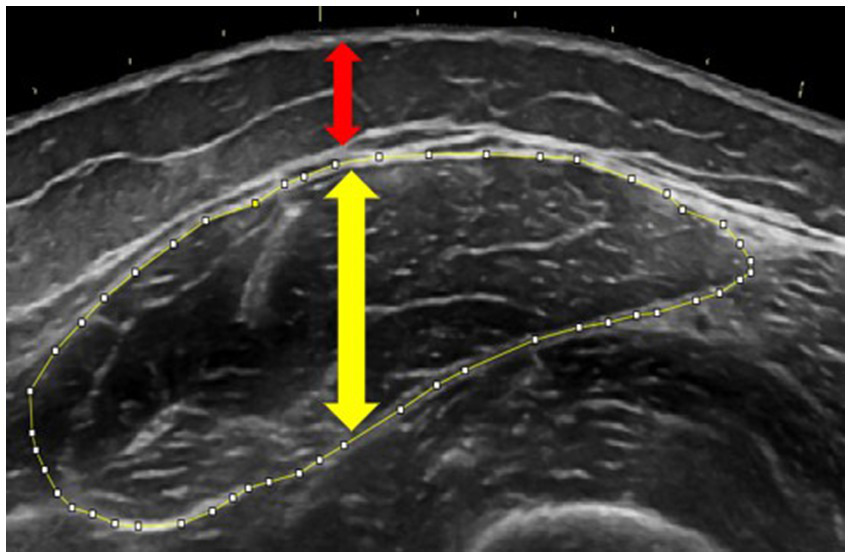

Leg extensor morphology was assessed with B-mode ultrasonography (Logiq e, GE Healthcare, Chicago, IL) following Herda et al. (24). With participants supine, panoramic transverse images were captured at standardized landmarks: rectus femoris (50% patella to greater trochanter distance), vastus lateralis (40% lateral-epicondyle to anterior superior iliac spine), and vastus medialis (20% medial-epicondyle to anterior superior iliac spine). A custom foam-padded probe guide ensured perpendicular sweeps while minimal pressure and ample gel prevented compression. ImageJ (National Institutes of Health, Bethesda, MD) was used to trace muscle cross-sectional area (mCSA, cm2) and extract mean echo intensity (mEI, grayscale score from 0 to 255) from the same region; muscle and subcutaneous-fat thickness were measured with the straight-line tool, as per Cleary et al. (25). Two participants did not complete this assessment. Figure 1 shows a representative rectus femoris image.

Figure 1. Ultrasonography image demonstrating measurements of muscle cross-sectional area (outlined in yellow), muscle thickness (yellow arrow), and subcutaneous adipose thickness (red arrow) of the rectus femoris. Tracing was performed using ImageJ software.